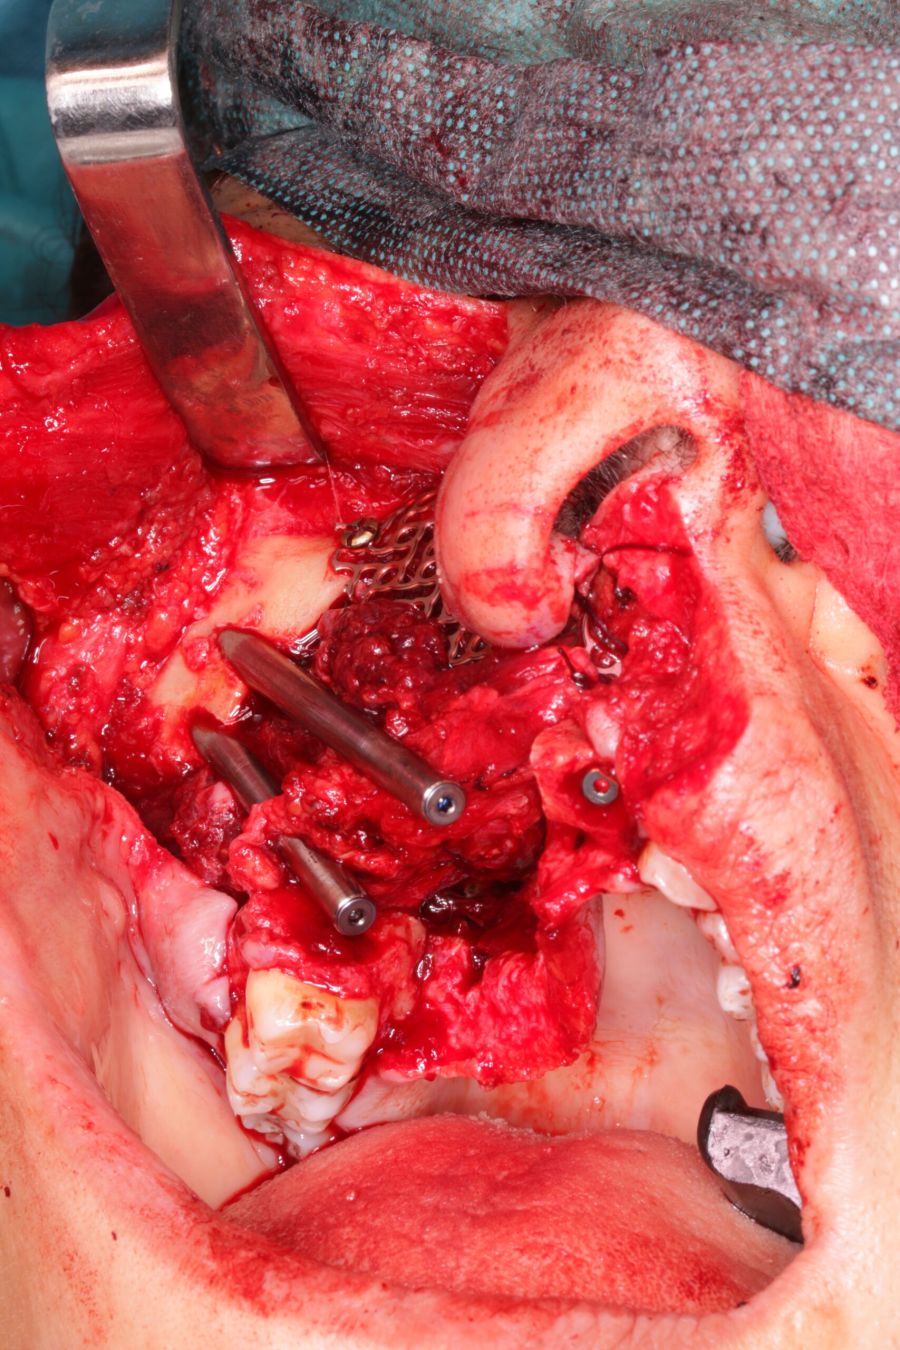

Bajo anestesia general, se realizó la resección quirúrgica junto con la fijación de dos placas preformadas y colocación simultánea de dos implantes cigomáticos y un implante endoóseo en posición del 2.1 (Figuras 5 y 6). Debido a la presencia de márgenes quirúrgicos comprometidos en el informe anatomopatológico, se indicó la administración de radioterapia adyuvante. Por este motivo, se decidió realizar un puente provisional dentosoportado de 1.7 a 2.3 (Figura 7) para mejorar la situación estética y funcional de la paciente durante todo el proceso y evitar un colapso de los tejidos blandos por la radioterapia. Para ello, se tallaron los molares (1.7, 1.6) e incisivo lateral y canino (2.2, 2.3), y se fabricó un puente fresado en polimetilmetacrilato (PMMA) con refuerzo metálico (Figuras 8 y 9).